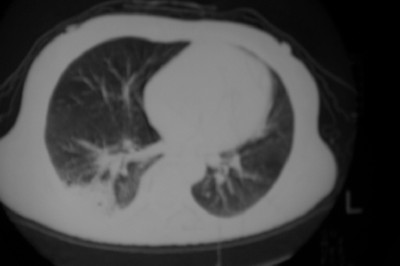

以下是引用天南地北在2007-4-10 1:49:00的发言:[br]考虑右下叶周围型肺癌伴肋骨转移。

以下是引用jone-baby在2007-4-10 8:45:00的发言:[br][br] [br] 患者[br]有发热史,x线片考虑肺脓肿.肺脓肿可以导致肋骨破坏吗?[br]脓肿可以排除吗? [br] [br] [br]

以下是引用林建春在2007-4-10 7:35:00的发言:[br]周围型肺癌侵犯肋骨

以下是引用liuyue在2007-4-10 7:56:00的发言:[br]周围型肺癌侵犯肋骨,左肺转移。

以下是引用zhangzhongshou在2007-4-10 10:24:00的发言:[br]右肺下叶背段厚壁空洞,伴胸膜改变、肋骨破坏,其内可见死骨、周围骨质硬化,左肺可见小结节影,[br]单纯影像学更支持结核。建议进一步检查。